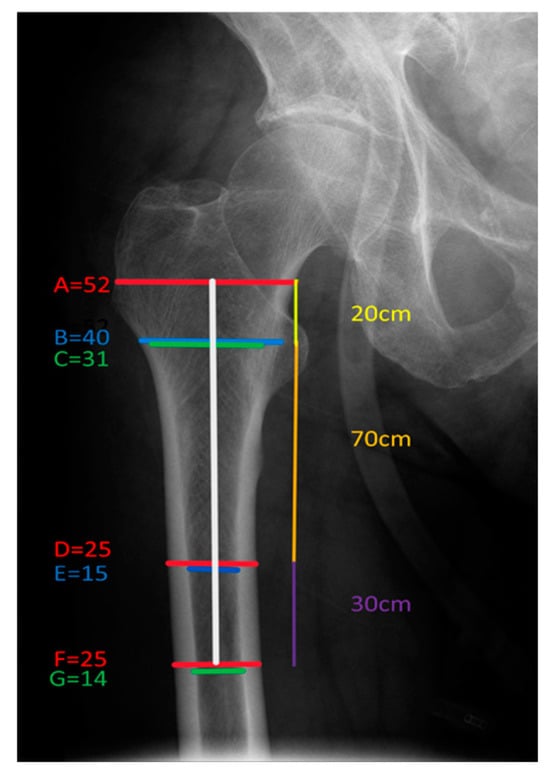

2.2. Radiography and Radiological Indices